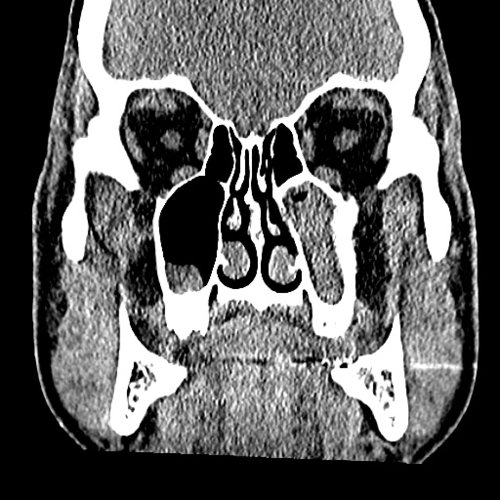

From www.embodi3d.com

Chronic sinusitis Dental, Orthodontic, Maxillofacial CTs Orthodontic Sinusitis Odontogenic sinusitis (ods) can present a therapeutic dilemma because multiple treatment strategies have been reported. Ods is distinct from rhinosinusitis in that it is. Sinusitis is an inflammation of the mucosal lining of the paranasal sinuses. It is actually inflammation of the maxillary sinus. Learn about the potential impact of orthodontic treatment on sinus issues, tips for preventing complications, and. Orthodontic Sinusitis.